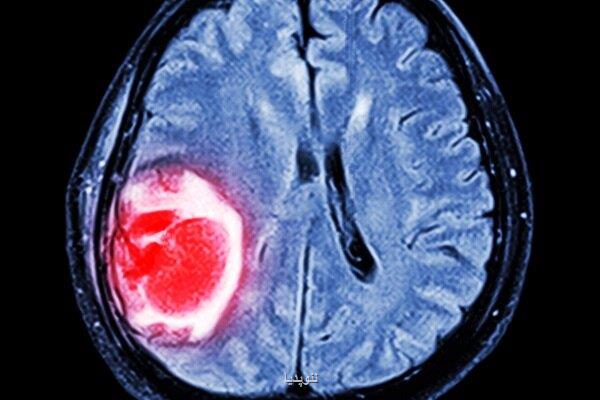

به گزارش نئوپدیا، محققان در چین و آمریکا برای توسعه یک درمان مبتنی بر نانوذرات گیاهی برای گلیوبلاستما (مرگبارترین سرطان مغز) با یکدیگر همکاری کردند.

به گزارش نئوپدیا به نقل از اینترستینگ انجینرینگ، این نانو ذرات که از فیتوکمیکال (phytochemical)هایی به نام باردوکسولون متیل (BM)ساخته شده اند برای نفوذ به سد خونی- مغزی و هدف گرفتن سلول های تومور به صورت مستقیم طراحی شده اند. فیتوکمیکال ها مواد بیواکتیو گیاهانی هستند که برپایه ساختار شیمیایی و عملکرد فیزیولوژی گروه بندی شده اند. محققان دانشگاه رمنین ووهان و دانشگاه یل این نانوذرات را به موش ها تزریق و مشاهده کرد آنها به صورت موفقیت آمیز سلول های تومور را شناسایی و به آنها حمله کردند. درمان فعلی این نوع از سرطان مغز شامل جراحی حذف تومور است. بعد از این فرآیند بیمار باید اشعه درمانی و شیمی درمانی انجام دهد اما سرطان امکان دارد با وجود درمان مقاومت کند. در نتیجه تأثیر درمان بر بیماری اندک خواهد بود. یک چالش مهم در این حوزه سد خونی-مغزی یا غشای حفاظتی دور مغز است. خیلی از داروها از این مانع رد نمی شوند و تاثیرگذاری آنها بر درمان بیماری هایی مانند گلیوبلاستوما اندک خواهد بود. نانو ذرات تازه توسعه یافته می تواند این چالش را برطرف کند. طبق پژوهش مولکول های گیاهی این درمان ذراتی ریز به وجود می آورند. این مواد بسیار ریز و حدود ۵۰ تا ۸۰ نانومتر قطر و ۱۷۰ نانومتر طول دارند.